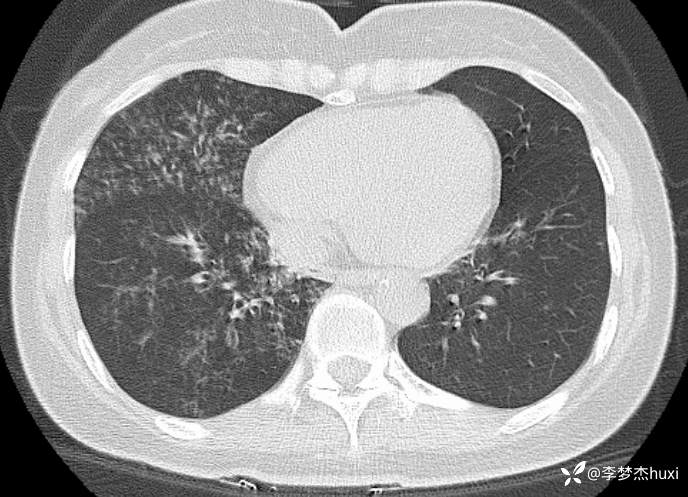

女性53岁,腮腺癌术后反复咳嗽、咳痰,胸部CT以树芽征为特点改变,最可能的是哪种疾病

【现病史及既往史】: 1.患者中年 女,患者于入院前5天无明显诱因出现咳嗽,咳痰,为黄绿色痰,量少,不易咳出,伴发热,最高体温不详,伴周身乏力,无胸痛,无呼吸困难,无恶心、呕吐,无腹痛、腹泻,无抽搐及意识障碍,院外未诊治,症状无好转,今患者及家属为进一步诊治前来我院就诊,门诊查胸部CT:右肺上叶占位性病变应考虑,右肺上叶空洞;右肺下叶占位?双肺炎症,支气管炎?右肺门淋巴结增大,双肺实性结节,纵隔结节,主动脉及冠状动脉钙化,右侧乳腺结节?建议结合超声,建议结合临床复查。门诊以“肺炎”收入院 。

2.既往高血压病史20余年,最高达180/?mmHg,目前口服“缬沙坦胶囊、硝苯地平控释片、酒石酸美托洛尔”等药物治疗,血压未监测;2008年因右侧腮腺腺样囊性癌于天津肿瘤医院行手术治疗,术后给予放化疗,2019年肿瘤原位复发,于北京大学口腔医院再次行手术治疗,2023-8发现肿瘤侵犯右耳道,目前口服仑伐替尼治疗约12个月;2023-11开始应用帕博利珠单抗注射液免疫治疗,患者右肺上叶占位,2024-7于沧州市中心医院行穿刺活检,病理:腺样囊性癌,2024-08于北京市某医院行“肺部射频消融术”;患者术后时常呛咳,否认“冠心病、糖尿病”病史,否认“肝炎”、“结核”等传染病史;否认外伤史,无输血史;否认食物、药物过敏史,预防接种史不详,系统回顾无特殊。。